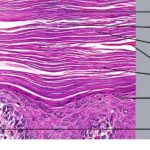

PATHOLOGY

Pathologic findings in pityriasis rubra pilaris vary according to the duration of the disease. The findings are most likely to be diagnostic in the acute phase, when hyperkeratosis, acanthosis with broad short rete ridges, and alternating orthokeratosis and parakeratosis oriented in both horizontal and vertical directions can be observed (see Pityriasis Rubra Pilaris At a Glance). Usually, there is a sparse superficial, perivascular lymphocytic infiltrate in the underlying dermis. Keratinous plugs of the follicular infundibula as well as perifollicular areas of parakeratosis may also be present. A prominent granular layer and dilated, but not tortuous, capillaries are features that help to distinguish pityriasis rubra pilaris from psoriasis, the most important differential diagnosis.